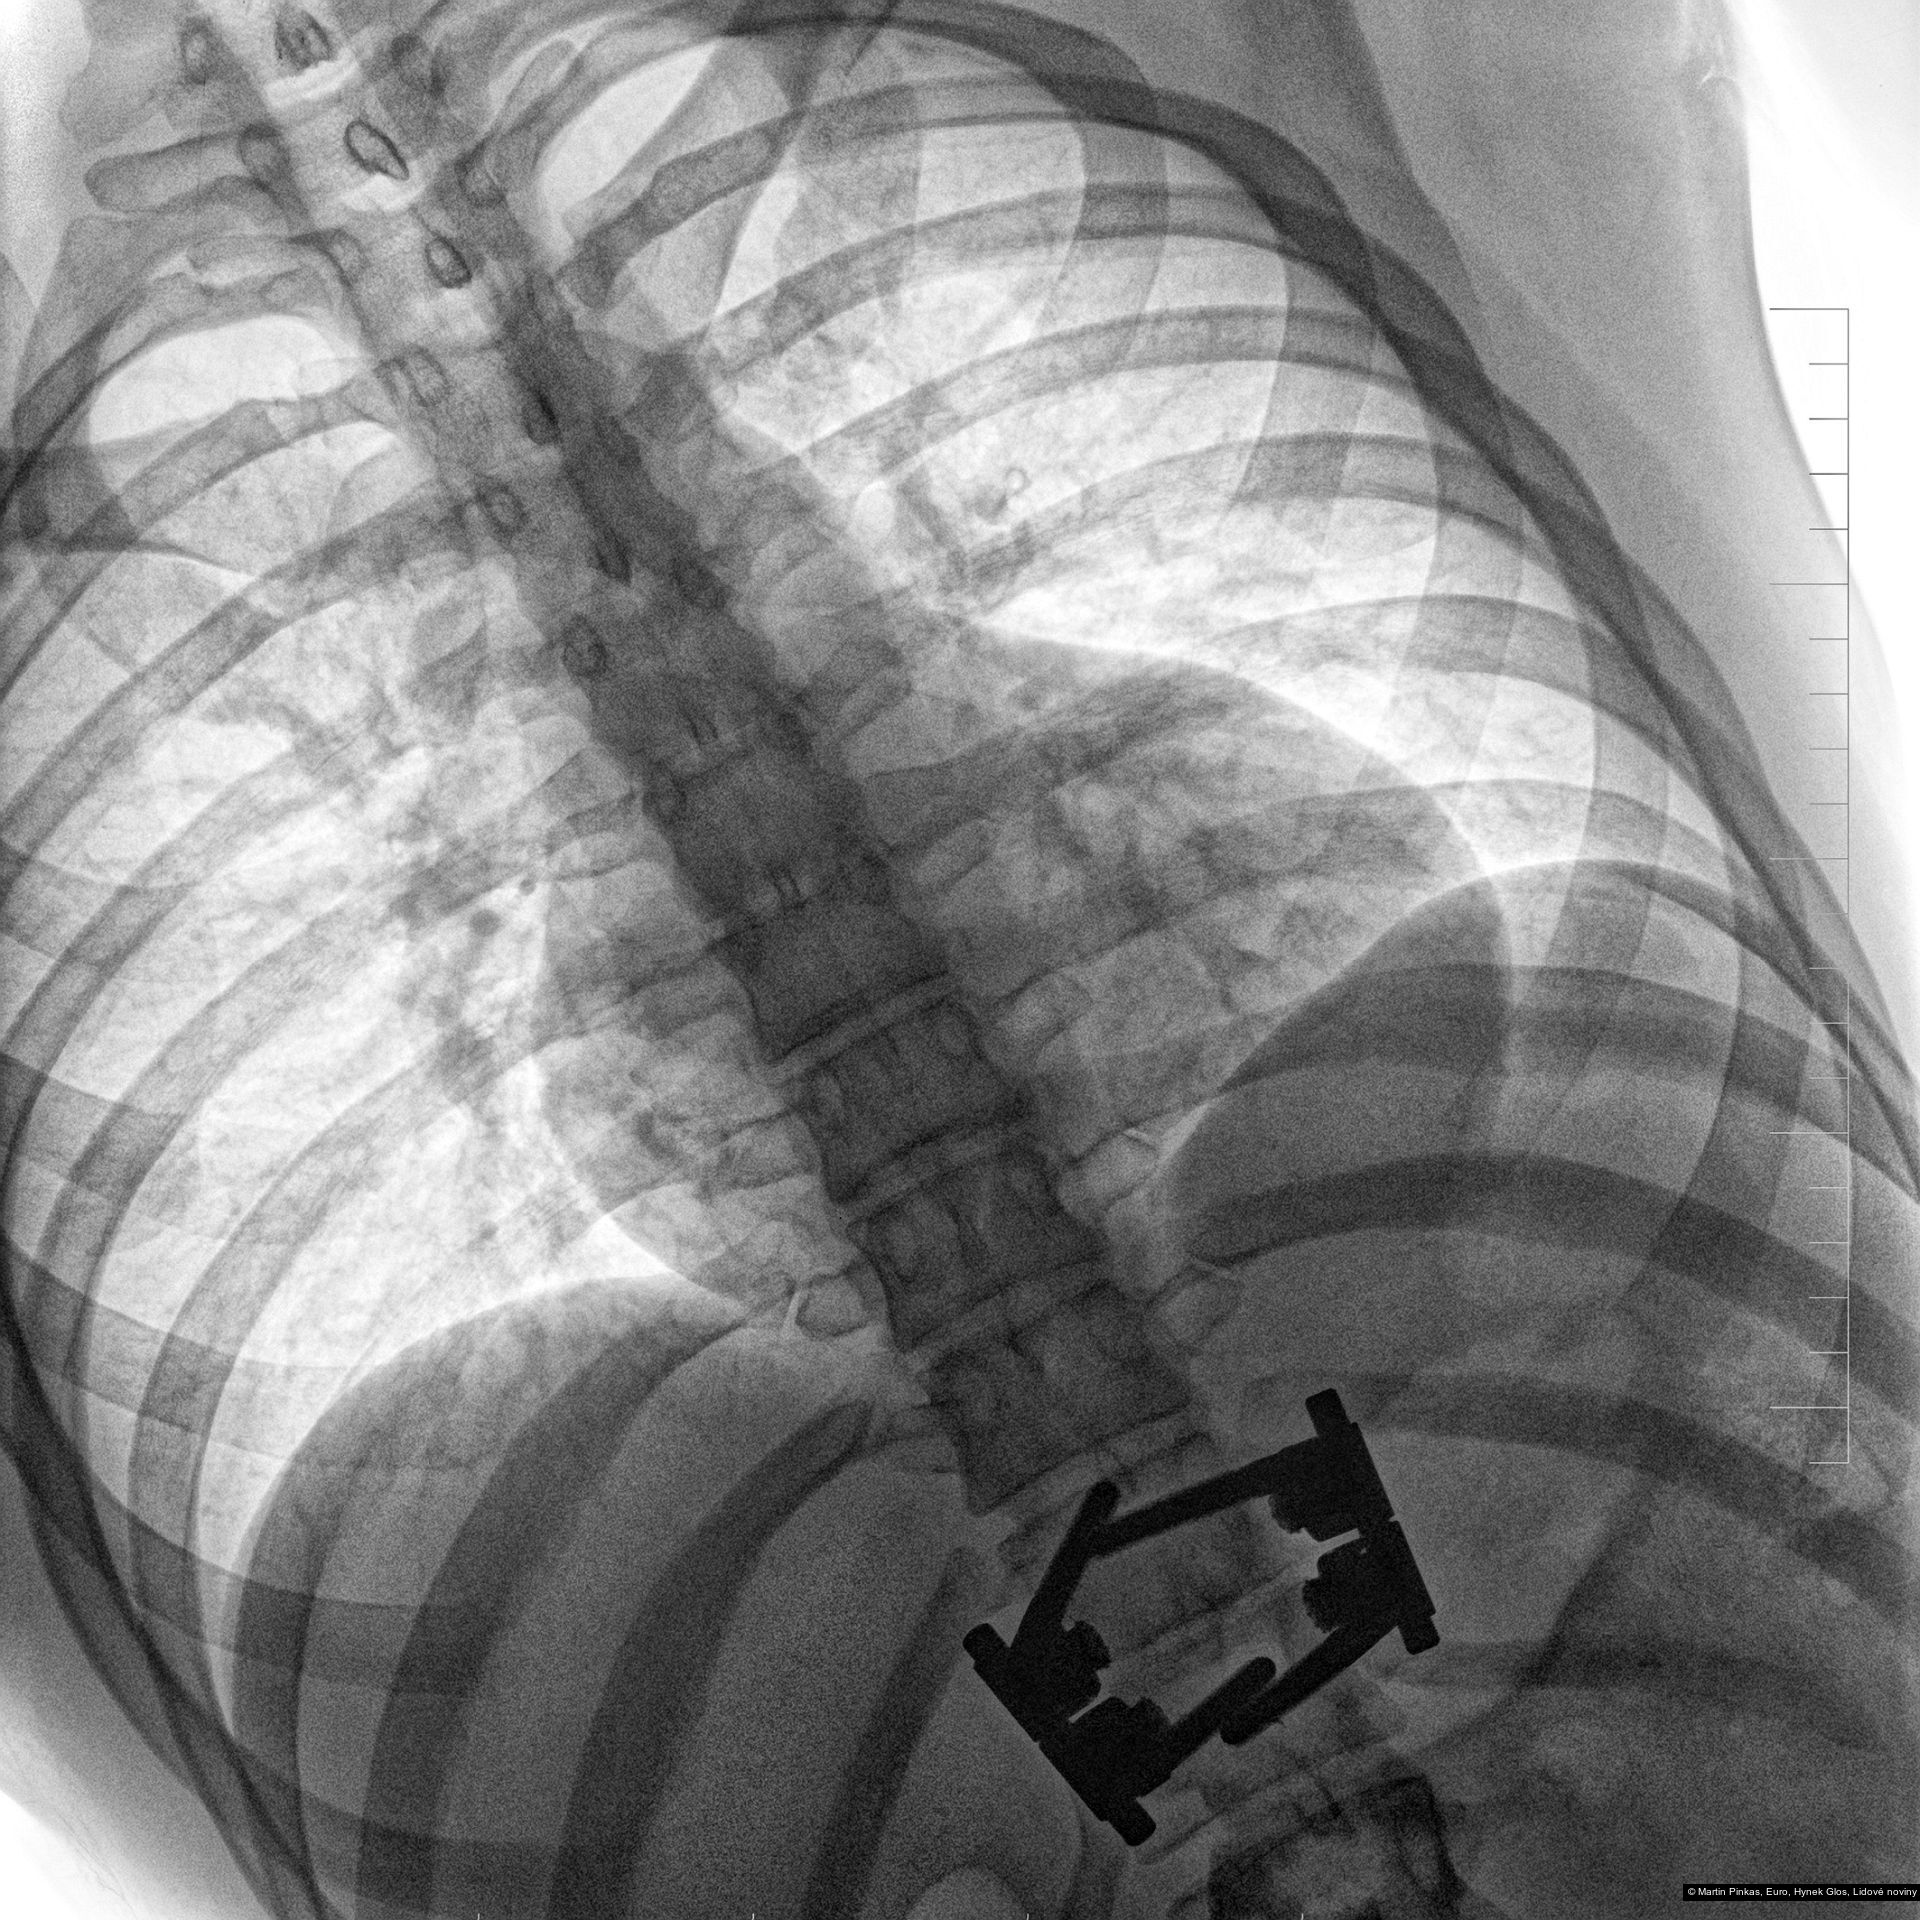

Příspěvek: X-portrait, nelékařské rentgenové portréty handicapovaných sportovců, Praha, Mostiště, 6.8. - 15.9.2010

Autor: Hynek Glos, Martin Pinkas

Příspěvek: X-portrait, nelékařské rentgenové portréty handicapovaných sportovců, Praha, Mostiště, 6.8. - 15.9.2010

Autor: Hynek Glos, Martin Pinkas

Příspěvek: X-portrait, nelékařské rentgenové portréty handicapovaných sportovců, Praha, Mostiště, 6.8. - 15.9.2010

Autor: Hynek Glos, Martin Pinkas

Příspěvek: X-portrait, nelékařské rentgenové portréty handicapovaných sportovců, Praha, Mostiště, 6.8. - 15.9.2010

Autor: Hynek Glos, Martin Pinkas

Příspěvek: X-portrait, nelékařské rentgenové portréty handicapovaných sportovců, Praha, Mostiště, 6.8. - 15.9.2010

Autor: Hynek Glos, Martin Pinkas

Příspěvek: X-portrait, nelékařské rentgenové portréty handicapovaných sportovců, Praha, Mostiště, 6.8. - 15.9.2010

Autor: Hynek Glos, Martin Pinkas

Příspěvek: X-portrait, nelékařské rentgenové portréty handicapovaných sportovců, Praha, Mostiště, 6.8. - 15.9.2010

Autor: Hynek Glos, Martin Pinkas

Příspěvek: X-portrait, nelékařské rentgenové portréty handicapovaných sportovců, Praha, Mostiště, 6.8. - 15.9.2010

Autor: Hynek Glos, Martin Pinkas

Příspěvek: X-portrait, nelékařské rentgenové portréty handicapovaných sportovců, Praha, Mostiště, 6.8. - 15.9.2010

Autor: Hynek Glos, Martin Pinkas